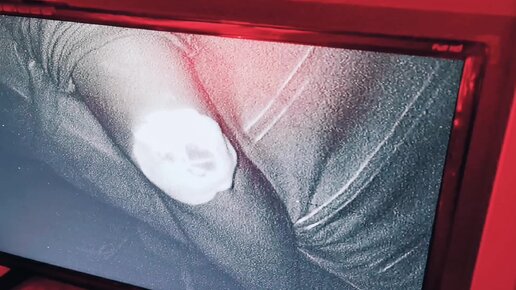

ВИДЕО "СЕАНС ФОТОДИНАМИЧЕСКОЙ ТЕРАПИИ, - ЛЕЧЕНИЕ АРТРОЗО-АРТРИТА КОЛЕННОГО СУСТАВА".